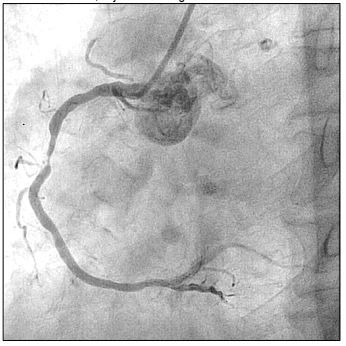

Paciente de 66 anos, relata queixa de dor torácica em aperto.

Procura atendimento médico onde realiza ECG que evidencia

IAM com supra de ST. Então, é levada à hemodinâmica onde é

realizado o exame, cujo achado segue abaixo:

Em relação à anormalidade evidenciada, assinale a alternativa que apresenta a coronária acometida.